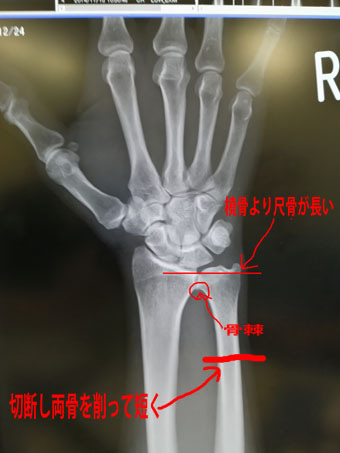

TFCC損傷尺骨突き上げ症候群druj不安定症入院手術尺骨短縮術ギプス手術跡レントゲン入院記録抜釘手術。

尺骨突き上げ症候群S-HANDクリニック 埼玉県さいたま市 手外科。

尺骨突き上げ症候群手の治療専門サイト。

尺骨突き上げ症候群長野整形外科クリニック。